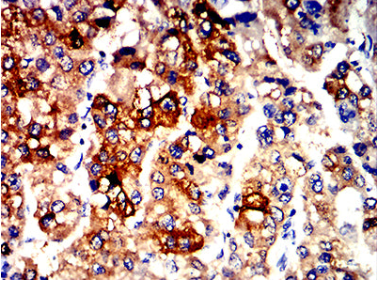

ALDH1L1 Mouse Monoclonal antibody[1B5E9]

The protein encoded by this gene catalyzes the conversion of 10-formyltetrahydrofolate, nicotinamide adenine dinucleotide phosphate (NADP+), and water to tetrahydrofolate, NADPH, and carbon dioxide. The encoded protein belongs to the aldehyde dehydrogenase family. Loss of function or expression of this gene is associated with decreased apoptosis, increased cell motility, and cancer progression. There is an antisense transcript that overlaps on the opposite strand with this gene locus. Alternative splicing results in multiple transcript variants.

Immunogen    Purified recombinant fragment of human ALDH1L1 (AA: 10-222) expressed in E. Coli.

IHC    1/200 - 1/1000